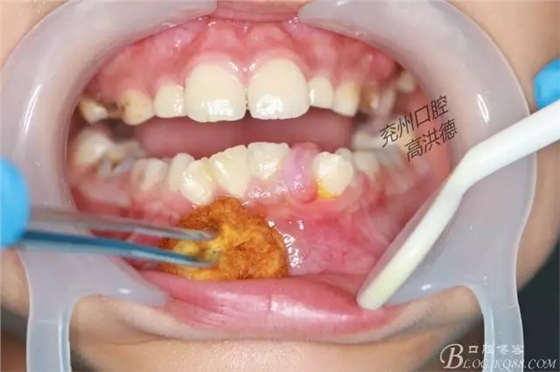

消毒,無痛麻醉儀注射

常規(guī)消毒上激光,切除模式

常規(guī)消毒

開始切除